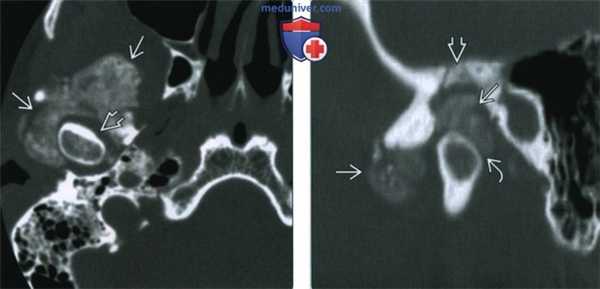

(Слева) При аксиальной КТ в костном окне, полученной на уровне основания черепа, визуализируется обширный обызвествленный участок вокруг мыщелка нижней челюсти справа. Обратите внимание на отсутствие патологических изменений со стороны суставного пространства вокруг мыщелка.

(Справа) Сагиттальная КТ в костном окне у этого же пациента позволяет лучше визуализировать обызвествления и оценить их расположение по отношению к височно-нижнечелюстному суставу. Обратите внимание на деминерализацию и эрозии костных структур, образующих суставную ямку, обусловливающие дефект средней черепной ямки. Нижнее суставное пространство сдавлено, но в остальном сохранно. (Слева) При МРТ Т2ВИ FS в аксиальной проекции у пациента с болезнью депонирования кальция пирофосфата возле правою височно-нижнечелюстного сустава визуализируется патологический участок с неоднородным, преимущественно гипоинтенсивным сигналом. Наблюдается жидкость в суставном пространстве вокруг головки мыщелка нижней челюсти.

(Справа) Сагиттальная КТ в костном окне у этого же пациента позволяет лучше визуализировать обызвествления и оценить их расположение по отношению к височно-нижнечелюстному суставу. Обратите внимание на деминерализацию и эрозии костных структур, образующих суставную ямку, обусловливающие дефект средней черепной ямки. Нижнее суставное пространство сдавлено, но в остальном сохранно.